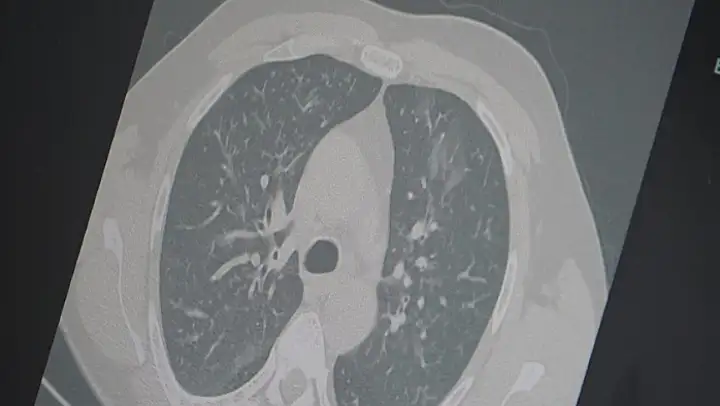

Dr. Özkaya, grip ve kovid 19'un zatürreye dönüşme riski taşıdığını vurgulayarak, 'Grip veya kovid sonrası birçok hastamızda hastalık akciğerlere iniyor ve zatürre olarak karşımıza çıkıyor. Hastaneye yatan hasta sayısında da artış gözlemliyoruz' şeklinde konuştu.

'En ufak grip benzeri şikayeti olan vatandaşlarımızın evlerinde dinlenmelerini öneriyoruz. Uzamış öksürük ve nefes darlığı yaşayanların ise mutlaka doktora başvurarak akciğer röntgeni çektirmeleri ve uygun tedaviyi almaları gerekiyor.'